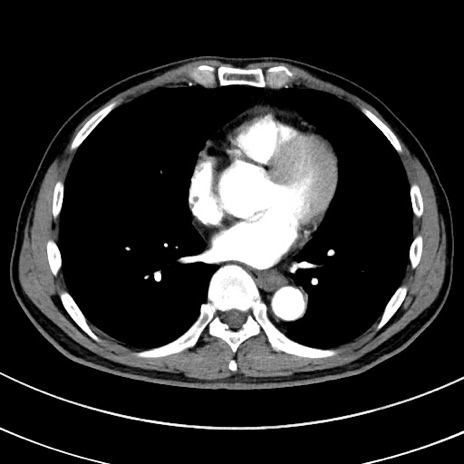

症例8(横断像)

【症例】 60歳代男性

【主訴】 黒色吐物

【現病歴】 4日前から嘔気自覚、2日前の朝食後にも嘔気あり、自分で手で嘔吐反射起こし嘔吐したところ血が混ざっていたため受診。

【既往歴】 5年前汎発性腹膜炎を伴う急性虫垂炎で手術、高血圧、前立腺肥大症、高脂血症

【身体所見】 腹部正中に手術癩痕あり 腹部平坦・軟圧痛なし膨満感あり

【データ】WBC 8400、CRP 4.54